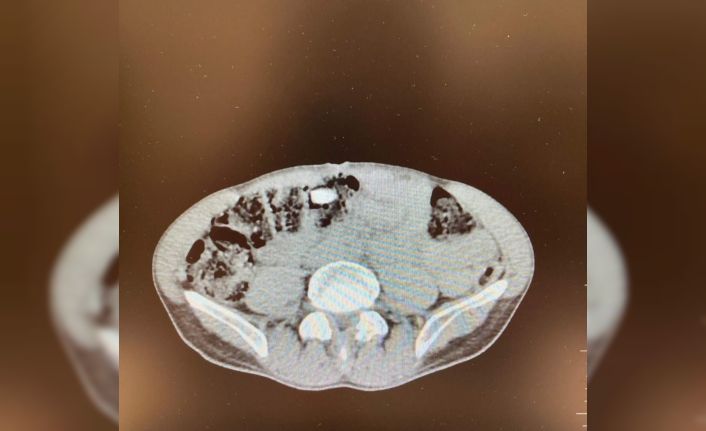

Denizli İl Emniyet Müdürlüğü Narkotik Suçlarla Mücadele Şube Müdürlüğünce uluslararası uyuşturucu madde ticaretinin önlenmesine yönelik çalışmalar devam ediyor. Yapılan incemeler ve değerlendirmeler sonucunda Denizli’ye havayoluyla yolculuk eden yabancı uyruklu şahsın uyuşturucu madde getireceği tespit edildi. Şüpheli, Narkotik Suçlarla Mücadele Şube Müdürlüğü ve Çardak Havalimanı Gümrük Muhafaza Bölge Amirliği görevlilerince müşterek yapılan çalışmalar neticesinde yakalandı. Şüphelinin eşyalarında yapılan aramalarda 6 parça halinde giysilere emdirilmiş şekilde 1 kilo 257 gram metamfetamin maddesi ele geçirildi. Yapılan iç beden muayenesinde ise 3 parça halinde 15 adet ecza hap ele geçirildi. "Uyuşturucu veya uyarıcı madde ticareti yapmak" suçundan adli makamlara sevk edilen şüpheli, tutuklanarak cezaevine gönderildi.